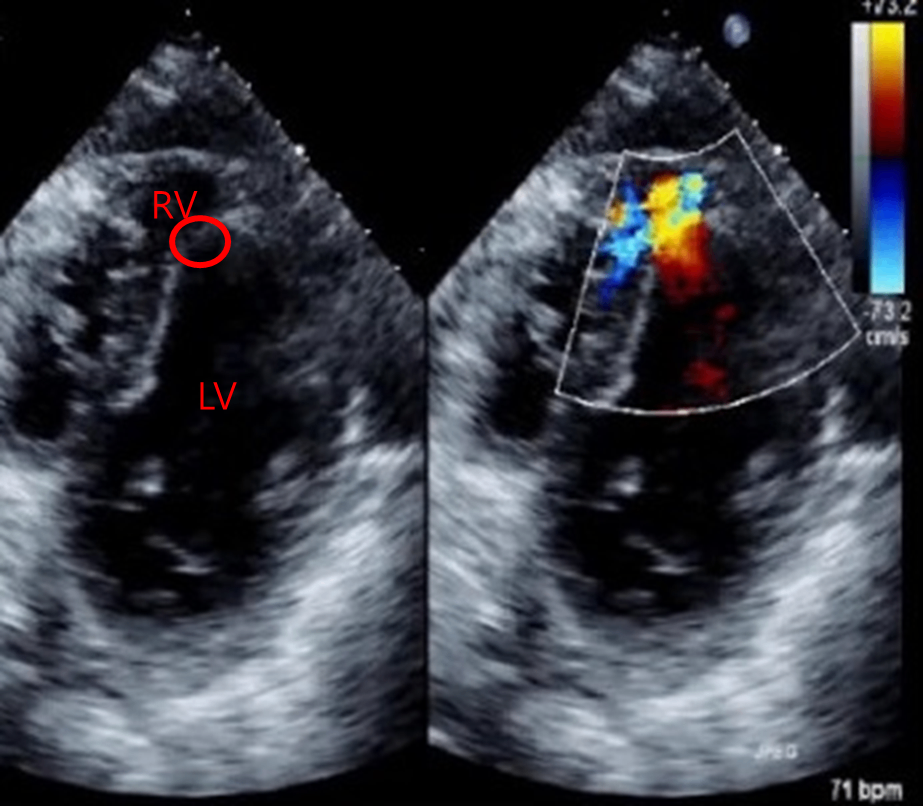

74세 여자가 30분 전부터 숨이 찬다며 병원에 왔다. 1주 전 심근경색증으로 관상동맥중재술을 받았다고 한다. 혈압 90/60 mmHg, 맥박 110회/분, 호흡 30회/분, 체온 37.5 ℃이다. 가슴 청진에서 양폐야에 거품소리가 들리고 복장뼈 좌하연에서 5/6도의 수축기 심잡음이 들린다. 심초음파검사 사진이다. 치료는?

Etc | Echo: Shunt flow across the interventricular septum, consistent with VSR |

Imp: 심실중격파열(interventricular septal rupture, VSR)

심근경색 1주 후 갑작스러운 폐부종과 함께 복장뼈 좌하연에서 수축기 심잡음이 들리고 심초음파에서 좌심실과 우심실 사이의 결손이 관찰되므로 외과적 봉합수술로 치료한다.

• 심초음파상 LV와 RV 사이의 와류가 확인된다. 따라서 VSR로 진단할 수 있으며, 현재 혈역학적으로 불안정하므로 응급 수술이 필요하다.